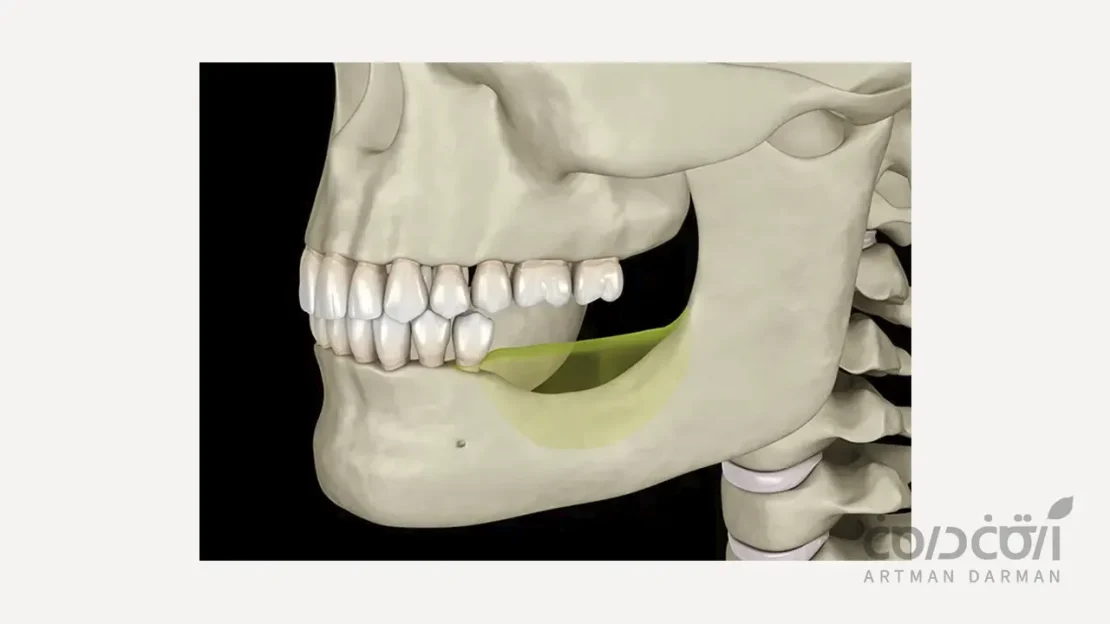

برای درک دقیق ضرورت پیوند استخوان برای ایمپلنت دندان، ابتدا باید یک فرآیند بیولوژیک طبیعی به نام “بازجذب یا آتروفی استخوان” را بشناسیم. استخوان آلوئولار، بخشی از استخوان فک است که ریشه دندان ها را در بر گرفته و از آن ها پشتیبانی می کند. این استخوان، یک بافت دینامیک و زنده است.

ریشه دندان های طبیعی از طریق الیاف بسیار ظریفی به نام لیگامان پریودنتال به استخوان متصل است. هر بار که عمل جویدن انجام می شود، نیروهای فانکشنال از طریق ریشه به استخوان آلوئولار اطراف منتقل می شود. این تحریکات مکانیکی مداوم، یک سیگنال بیولوژیک به بدن ارسال می کند که این ناحیه از استخوان فعال و ضروری است و باید تراکم و حجم خود را حفظ کند. این فرآیند، استخوان را سالم و متراکم نگه می دارد.

وقتی دندان از دست می رود ….

پس از کشیدن یا از دست رفتن یک دندان، این انتقال نیروی فیزیولوژیک متوقف می شود. در غیاب این تحریکات، بدن دیگر لزومی به حفظ این حجم از استخوان نمی بیند و فرآیند بازجذب (Resorption) را آغاز می کند.

در نتیجه سلول هایی به نام استئوکلاست ها فعال شده و به تدریج بافت استخوانی را تحلیل می برند. این تحلیل، هم در بعد ارتفاع و هم در بعد عرض استخوان رخ می دهد و بیشترین شدت آن در ۶ تا ۱۲ ماه اول پس از غیبت دندان است. معمولاً در بیشتر موارد اگر فاصله بین غیبت دندانی و کاشت ایمپلنت زیاد باشد نیاز به پیوند استخوان برای ایمپلنت وجود دارد.